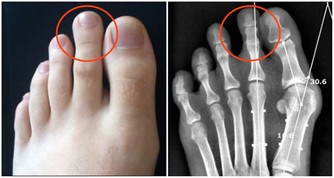

便秘、肥胖、高血壓、糖尿病、脂肪肝、肝炎、痛風、更年期障礙等症狀也有所改善。